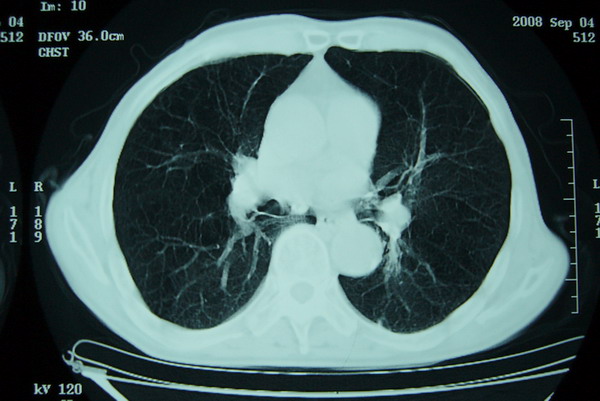

分叶及少量边缘性钙化,老年人,周围性肺癌首先考虑。

右上肺一不规则团块,边缘有分叶和毛刺,纵隔有淋巴结肿大。右肺周围性肺癌首先考虑。